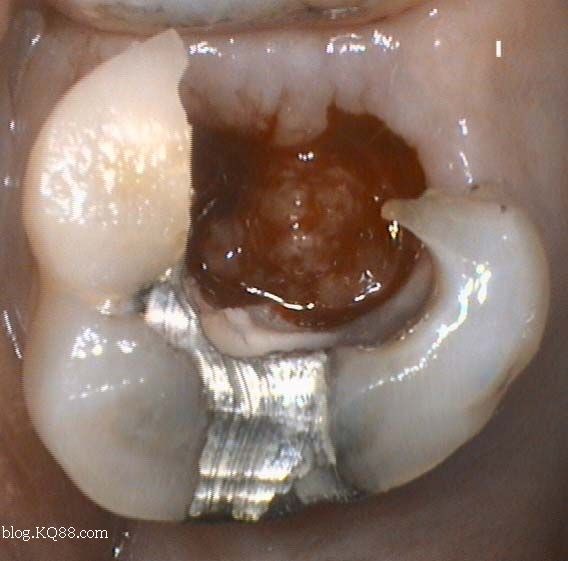

1、口腔鏡檢查:通過(guò)口腔鏡檢查,可以清晰地觀察到牙齒表面的牙洞以及牙洞內(nèi)的情況,醫(yī)生可以判斷牙洞是否已深入牙髓,并評(píng)估病情嚴(yán)重程度。

2、探診檢查:使用牙科探針檢查牙洞周圍組織的健康狀況,了解牙洞深度及與牙髓的關(guān)系。